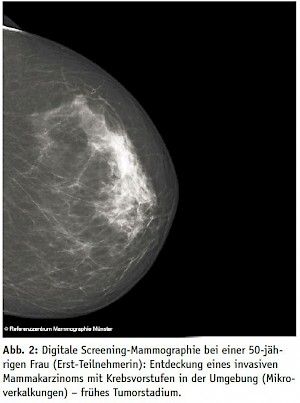

Ja, wobei sehr dichtes Gewebe mit dem Grad 4 ab 50 Jahren, also Frauen im MSP, wirklich die Ausnahme ist. Die digitale Mammographietechnik, die heute im Screening Standard ist, durchdringt dichtes Gewebe inzwischen viel besser als die analoge Röntgentechnik noch vor zehn Jahren. Wir haben gerade in Münster analysiert, ab welcher Dichte die mammographische Sensitivität zurückgeht. Wir haben gefunden - anders als man das so liest - dass eine Sensitivitätseinschränkung nur bei extrem dichtem Drüsengewebe der Stufe 4 auftritt. Bei Frauen mit einer Dichte 1–3 haben wir keinen wesentlichen Unterschied in der Programmsensitivität gefunden. In unserer Studie ist nur bei fünf Prozent der Frauen das Mammographie-Screening-Programm mit einem zweijährigen Intervall deutlich unterdurchschnittlich. Bei diesen Frauen muss man darüber nachdenken, ob man ihre Diagnostik ergänzt.